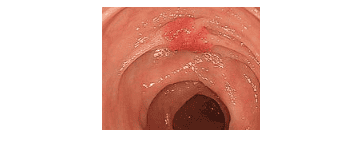

3. Đặc điểm của polyp ung thư hóa trên hình ảnh nội soi thông thường

Đặc điểm của một số polyp nghi ung thư hóa: bề mặt có khuynh hướng lan rộng, bề mặt polyp có loét hoặc viêm trợt, các nếp niêm mạc ruột hội tụ về phía polyp, polyp dạng “đặc”, polyp dạng lõm với phần trung tâm nhô lên.

Đối với những dạng hình ảnh như vậy, bác sĩ nội soi cần cân nhắc trước khi cắt polyp, vì có thể mức độ ung thư xâm lấn của polyp đã đến lớp dưới niêm, và việc cắt polyp qua nội soi không đảm bảo an toàn mặt ung thư.